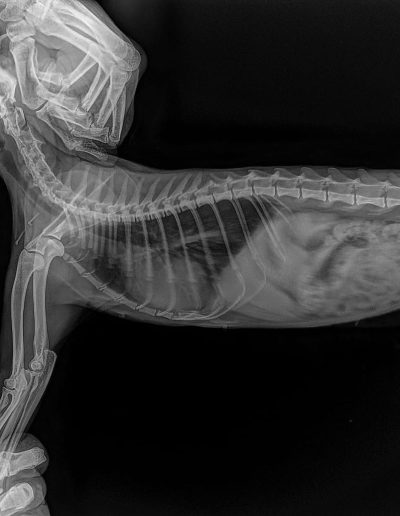

Taxi 6 months, Hit by a car and had a leg Amputation. Stayed more than 8 months at vet and then went to our kahu shelter to get his vaccines and the care need it